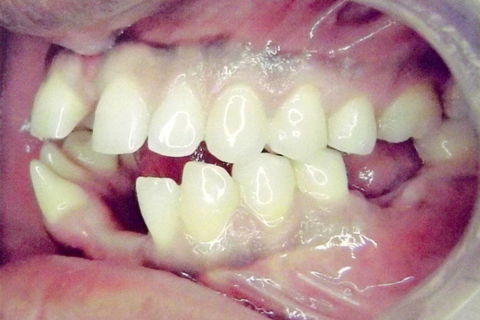

fotos iniciais do caso.

Paciente do sexo masculino, 36 anos, brauifacial. Relatava que os Diastemas lhe incomodavam muito, e em tratamento anterior o profissional fez exo de 2 incisivos centrais inferiores e instalou Prótese movel com 4 incisivos, após um tempo de uso a prótese começou a incomodar. em planejamento com o implantodontista ficou definido o fechamento dos diastemas e reabilitação dos elementos 41 e 31 com implantes.